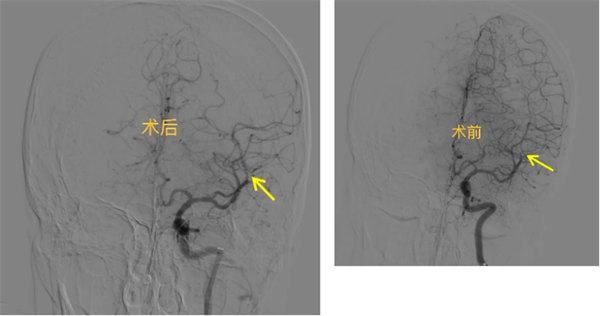

轉科第二天,王先生突然出現不能理解家人講話,答非所問,“上一秒還好好地和我交流,怎么突然就不行了”王先生的妻子焦急地說。侯卓醫生評估了病情后考慮新發腦梗死,NIHSS評分7分,并將病情立即上報科主任席聰。考慮到患者有上消化道出血病史,無法再次溶栓,侯卓醫師便安排王先生急診行顱腦CTA及灌注成像,同時請席聰評估介入取栓可能性,經檢查,王先生左側大腦中動脈M2段閉塞,有大范圍缺血灶,未見明顯梗死。

席聰考慮有急診腦動脈介入取栓指征,并告知王先生家屬介入取栓的必要性及風險,該病為顱內大動脈閉塞,危險性極高,此時萬分危急,每晚一分鐘治療患者的預后越差,可能終身殘疾甚至有生命危險,且王先生的癥狀還在波動,出現了不能講話的情況,王先生家屬決定采用取栓治療,在主任席聰、副主任醫師關建兵等介入團隊高效配合下,不到1小時,便開通了王先生左側大腦中動脈急性閉塞血管。術后,患者失語癥狀即刻完全好轉,NHISS評分4分。